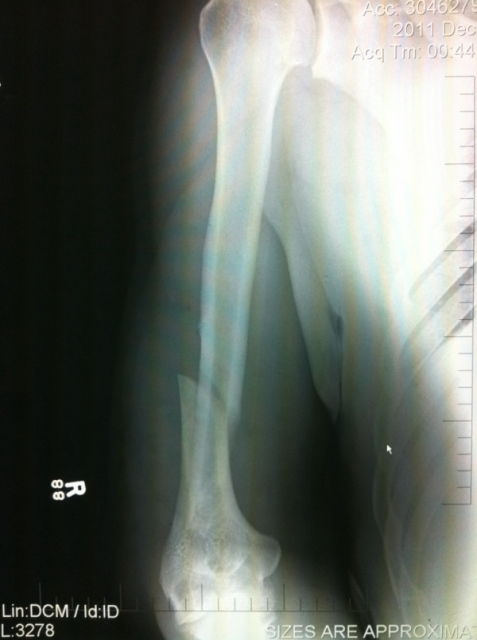

Нет особой необходимости напоминать, что, в отличие от Фрэнка Мира, его оппонент по UFC 140 – бразилец Big Nog заполучил перелом руки после проведенного болевого «кимура».

К счастью, у фанатов Родриго Ногейра появился повод для оптимизма – травма их любимца не требует оперативного вмешательства, дело может обойтись ношением фиксирующих приспособлений. В любом случае, бойцу понадобится не менее 9 месяцев на реабилитацию.